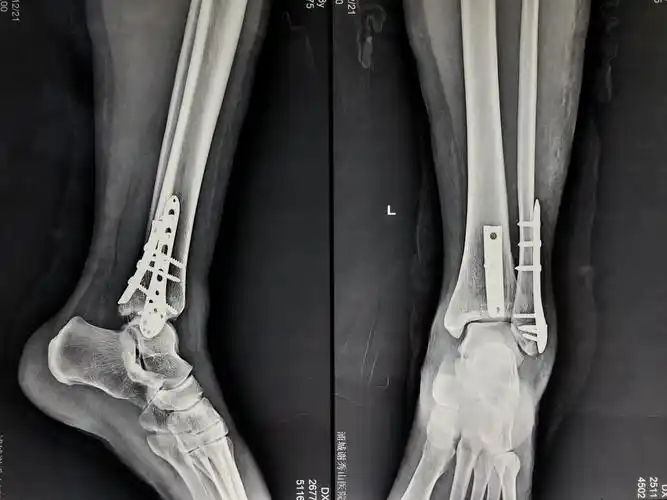

跟骨钢板_加压接骨板系统_苏州苏南捷迈得医疗器械有限公司

跟骨骨折重建钢板内固定

后踝1/3圆型钢板固定,钢板薄,好塑形,更伏贴

文登整骨医院首例微创双窗入路钢板内固定治疗跟骨骨折

跟骨加压接骨板

跟骨骨折入路,层次及重建钢板内固定